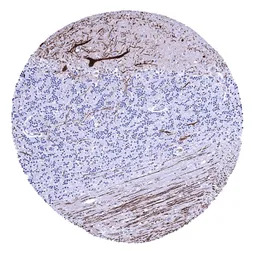

IHC-P analysis of human colon mucosa tissue section using GTX04454 Calbindin antibody [MSVA-471M] HistoMAX.

Calbindin immunostaining is absent in all cells of the colon mucosa.